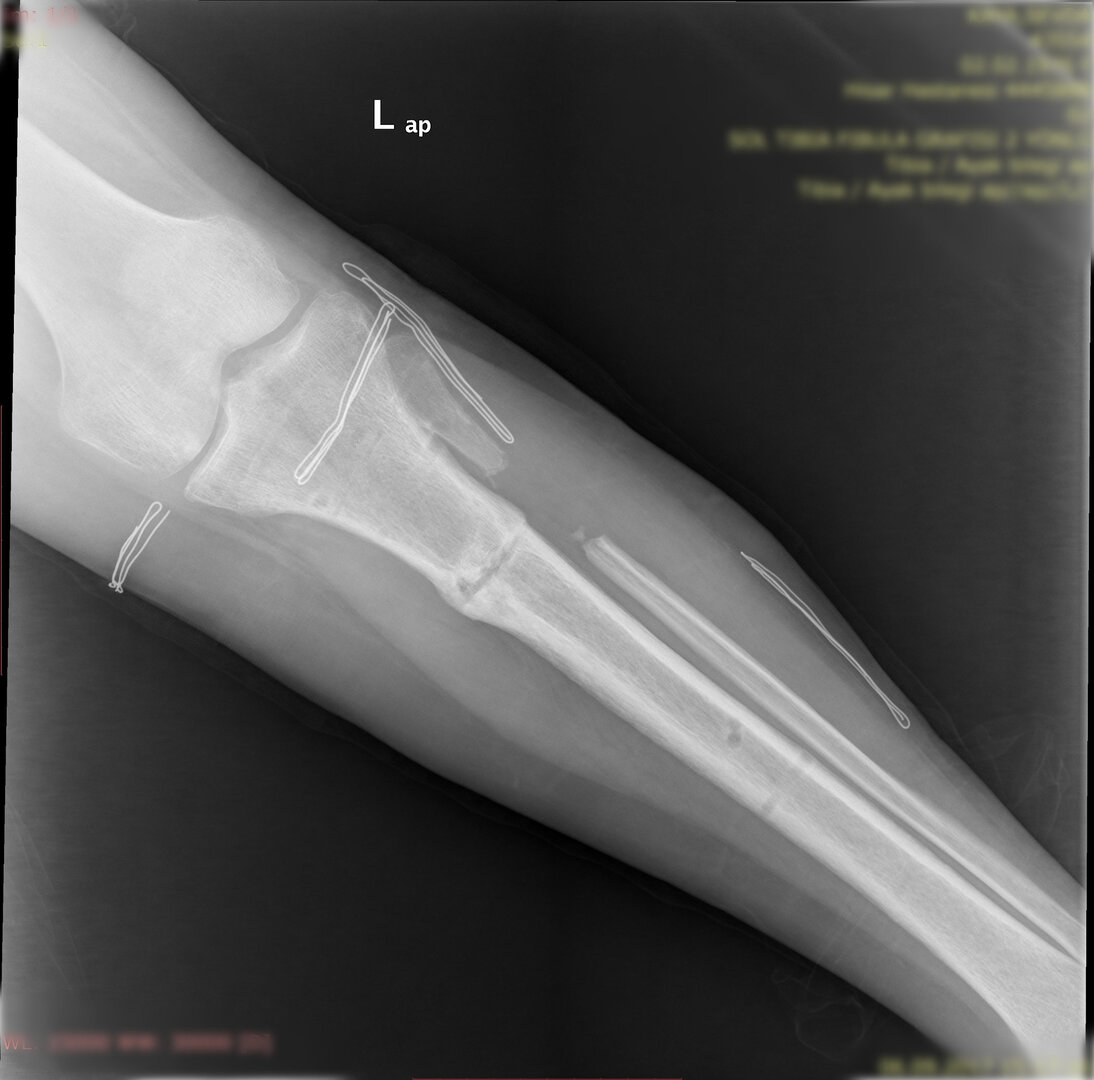

Deformitenin yeri ve miktarına bağlı olarak bilgisayar destekli sirküler eksternal fiksatör ile tedrici düzeltme yapılabilir. Bu sistemin avantajı düzeltme esnasında sistemle oynayarak yeni düzenlemeler yapmanıza izin vermesidir.

Diğer bir yöntem akut olarak düzeltme yöntemidir. Bu yöntemde kemiğe uygulanılan tespit yöntemi plak-vida kombinasyonu olabileceği gibi bir intramedüller çivi de olabilir.

Hangi tespit yöntemini kullanacağınıza deformitenin yeri ve miktarına göre karar vermek gereklidir.

Bu ameliyat öncesi bir deformite analizi yapılıp hangi kemikte, normalden ne kadar sapma olduğu tespit edilir. Daha sonra bu kemiğe yine ostetomi yapılarak bu anormal sapma düzeltilir.  Bu düzeltme plak-vida veya intramedüller çivi ile akut olarak düzeltilebileceği gibi bilgisayar destekli sirküler eksternal fiksatör ile tedrici olarak ta yapılabilir. Hangi yöntemin hangi hasta için uygun olacağına hasta özelinde karar veriyoruz, ne tür cerrahi tedavi olması gerektiğini danışabilirsiniz.

Büyütmek için üzerine tıklayınız.